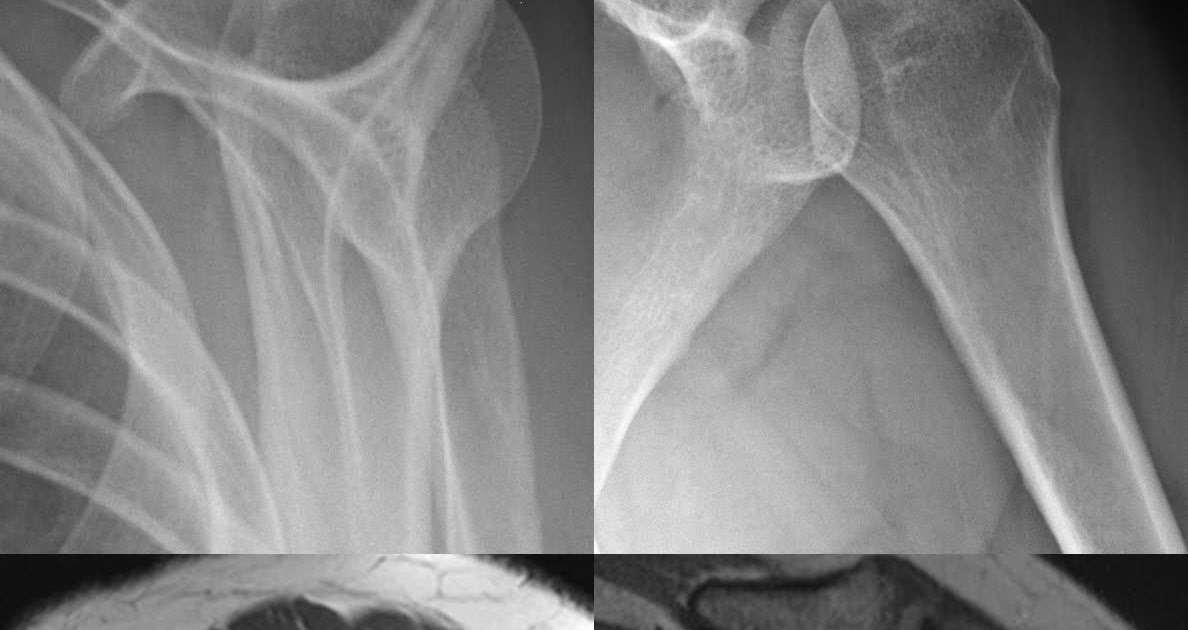

Roentgen Ray Reader Calcium Hydroxyapatite Deposition Disease Shoulder How Does Calcium Build Up In Your Shoulder Calcium deposits, or calcification, can occur when. Calcific tendonitis develops when calcium deposits build up in your tendons or muscles. Effective treatment can help to decrease the pain, improve shoulder function, and lessen the time with which you have to manage symptoms. Calcific tendonitis (or tendinitis) occurs when calcium deposits build up in your muscles or tendons. Sometimes pain, swelling. How Does Calcium Build Up In Your Shoulder.

Fotka „Film Xray shoulder radiograph showing calcium deposit on How Does Calcium Build Up In Your Shoulder Calcific tendonitis develops when calcium deposits build up in your tendons or muscles. Calcific tendonitis is caused by calcium build up in your rotator cuff tendons (that attach muscles to the bone). Typically treatment starts with simple, noninvasive steps. Effective treatment can help to decrease the pain, improve shoulder function, and lessen the time with which you have to manage. How Does Calcium Build Up In Your Shoulder.